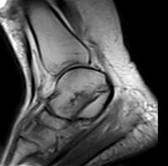

Рис. 4. Левый – полный разрыв задней малоберцово-таранной связки (стрелкой показана часть связки в точке фиксации к малоберцовой кости). Правый – гематома в зоне повреждения (×). |

| Рис. 5. Разрыв передней большеберцово-таранной связки; признаки консолидации перелома внутренней лодыжки (белая стрелка). |